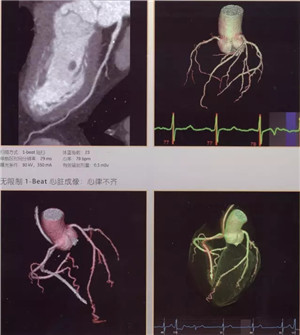

扫描速度超快:仅需0.28秒,不受心率快慢限制,只需一个心跳即完成精准的心脏CT检查,成为无创确诊冠心病的最佳检查手段。

图像分辨超清:0.23毫米的空间分辨率,对于2毫米冠脉支架的细节和支架内再狭窄清晰可辨;可超早期发现微小肿瘤病变。